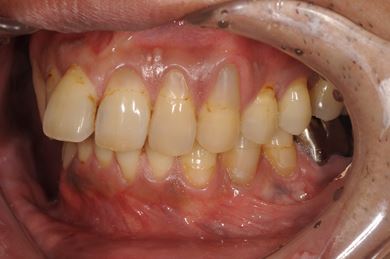

インプラントの症例写真 IMPLANT

インプラント治療+セラミック治療

| 性別/年齢 | 男性 / 36歳 | ||||||||||||||||||||||||||||||||

| 主訴 | インプラント治療と、その他全体的に歯の治療を希望。 | ||||||||||||||||||||||||||||||||

| 治療方針 | 欠損部分をインプラント治療にて、機能的・審美的回復を行う。 | ||||||||||||||||||||||||||||||||

| 治療内容 | インプラント2本、メタルボンドセラミッククラウン3本(メタルボンド用土台1本) | ||||||||||||||||||||||||||||||||

| 総治療費 | 629,685円 | ||||||||||||||||||||||||||||||||

| 治療期間 | 1年5ヶ月 |